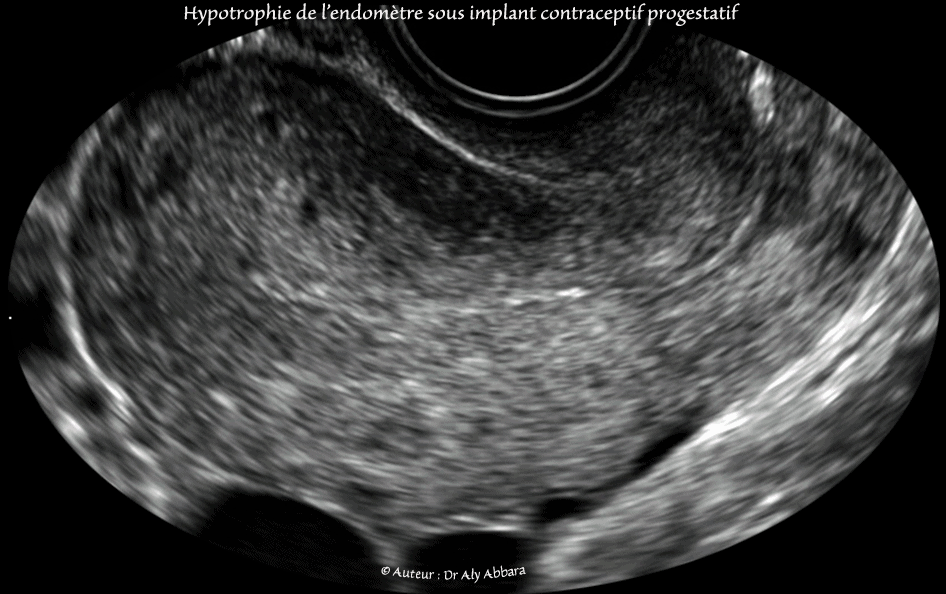

Utérus : l'aspect échographique habituel de l'endomètre hypotrophié sous l'effect d'une contraception par implant progestatif :

Échographiquement, on observe :

• Un endomètre très fin tapissant les parois antérieure et postérieure de la cavité utérine.

• L'épaissuer des deux endomètres réunis, antérieur et postérieur ne dépasse pas les 2 mm.

• Le symptôme clinique associé est une métrorragie répétitive et anarchique dans la durée et et dans l'intervalle entre deux saignements gynécologiques.